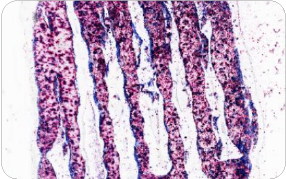

3D打印骨材料切磨片 Masson染色

鉑金植入血管切磨片

亞甲基藍(lán)-品紅染色

小鼠顱骨切磨片 VG染色 80x

比格犬下頜骨切磨片 HE染色

比格犬下頜切磨片 甲苯胺藍(lán)染色

骨切磨片 HE染色

人工血管鈦合金支架切磨片 HE染色

人工血管鈦合金支架切磨片

HE染色 40×

骨與聚合物切磨片 Von Kossa染色

犬下頜骨切磨片 Masson染色

犬下頜骨鈦合金植體切磨片

Masson染色 20×

犬-下頜骨-鈦合金植體 Masson染色 40× 高清掃描

犬-下頜骨-鈦合金植體 HE染色 40× 高清掃描

小鼠顱骨 VG染色 40× 高清掃描

羊主動脈弓-人工血管 HE染色 40× 高清掃描